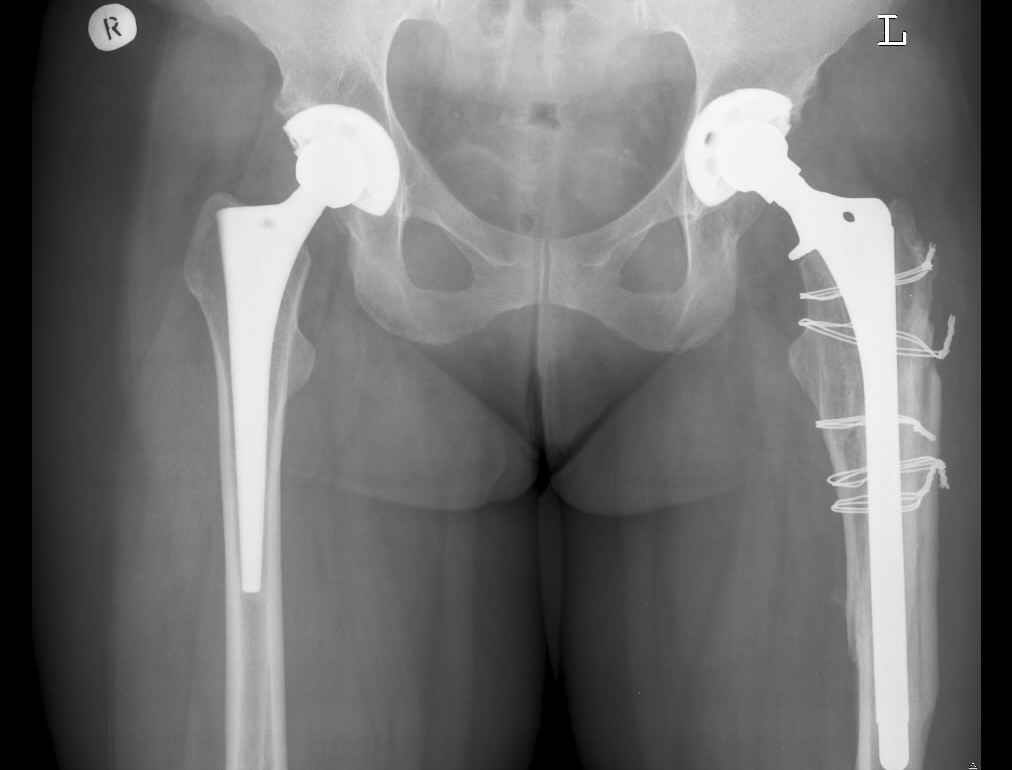

Добрый день!Мужчина, 39 лет., инв. II гр. 27.05.06 получил травму, после неудачного разворота с опорой на ногу почувствовал хруст и резкую боль.

Анамнез: Болеет с 1995 года. В 2000 и 2001 годах произведено тотальное эндопротезирование обоих тазобедренных суставов (сначала левого затем правого). Сейчас в области левого бедра в в/3 имеется резкий отек, боль, крепитация. Диагноз:Состояние после тотального эндопротезирования обеих Т\Б суставов, перелом в/3 левого бедра. Нога уложена на шину Беллера с дисциплинирующим вытяжением. Тактика оперативного лечения? Заранее благодарю! С уважением, А.В.Владзимирский Донецкий НИИ травматологии и ортопедии

В очередной раз вызывает удивление установка биполяра у молодого пациента, но дело не в этом. Имеется перелом с нестабильностью бедренного цементного компонента. Значительный дефект костной ткани проксимального отдела бедра.

Следует убрать ножку и остатки цемента, заменить на Вагнеровскую ножку (в крайнем случае на длинную цементную), добавить костную пластику проксимального отдела. Тазовый компонент заодно заменить на бесцементный.

Уважаемый Антон,

По Ванкуверовской классификации это 2А тип перипротезного перелома на фоне нестабильности ножки эндопротеза и остеолиза проксимального отдела бедра. Решение - удаление предыдущей ножки, имплантация ножки дистальной фиксации. Канал виден на ограниченном участке, исходя из увиденного, я бы предпочел цилиндрическую ножку 200 мм полнопокрытую. Фрагменты собрал бы вокруг ножки серкляжами. Если будут мелкие фрагменты, то есть смысл взять кортикальные аллографты и поджать фрагменты по типу вязанки хвороста. Отношение к чипсам двоякое - на любителя, главное - надежная дистальная фиксация ножки, обеспечивающая первичную стабильность. Что-то похожее мы оперировали несколько лет назад, качество первичных Р-грамм оставляет желать лучшего, но суть понятна. Результаты через 3 года.